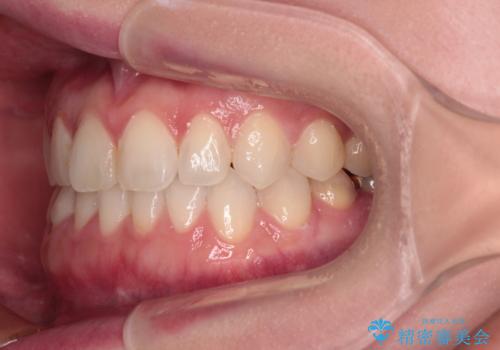

前歯のデコボコをすっきりと インビザライン矯正

- 前歯のデコボコを治したいとのことで来院された患者様です。

下顎が前方位にある方であったため、下顎の歯列全体の後方移動とIPR(歯と歯の間を削る)によってデコボコが解消するように設計し、インビザラインにより治療を行うこととしました。

装着時間が守れず、当初の予定よりも長期間必要となりました。